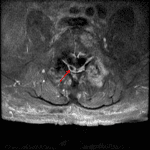

- T2/STIR signal hyperintensity and enhancement in the left L4-L5 facet joint, the adjacent articular pillars, and in the surrounding soft tissues with multiple subcentimeter peripherally-enhancing collections in the L4-L5 interspinous ligament and posterior paraspinal soft tissues

- Epidural enhancing soft tissue at the level of L5 with a 1 cm peripherally-enhancing collection in the right dorsal epidural space at this level

Discitis/osteomyelitis, septic facet arthritis, and epidural abscess

Findings consistent with left L4-L5 septic facet arthritis with associated osteomyelitis involving the adjacent articular pillars and surrounding phlegmon with intermixed scattered subcentimeter posterior paraspinal abscesses. Contiguous epidural phlegmon at the level of L5 with a 1 cm epidural abscess in the right dorsal epidural space.